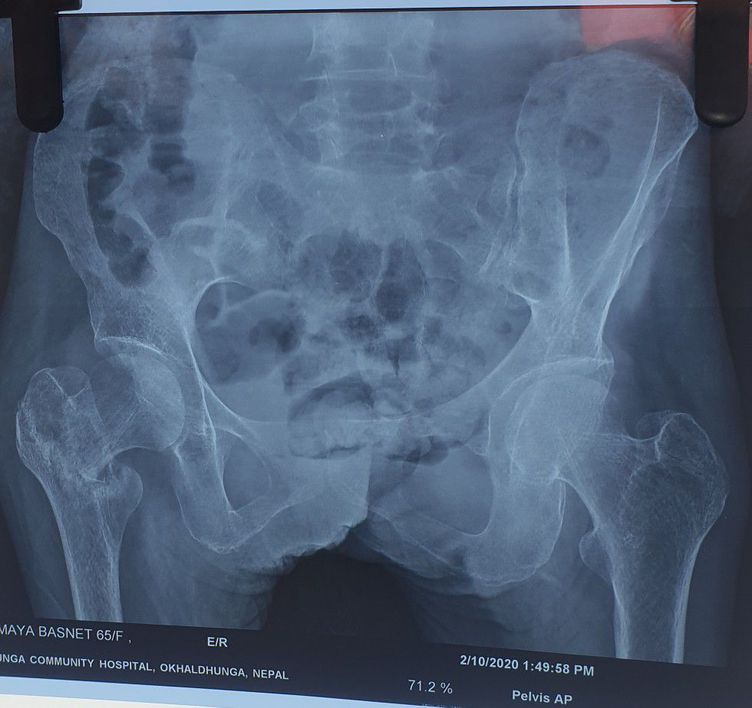

Right surgical neck of humerus fracture of femur.